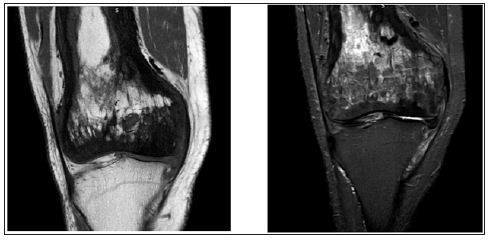

A 56-year-old male presented to us with severe disabling pain in his right knee affecting his day to day activities and which failed to respond to conservative measures. His plain radiographs showed mixed sclerotic and lytic lesions involving the entire shaft of the femur and a diagnosis of Paget’s was made on the typical radiological signs [6] on plain radiographs (Figures 1 & 2) and MRI (Figure 3). There was an anterolateral bowing of the femur about 100 and knee arthrosis changes with intra-articular varus deformity. There was no involvement of the tibia (Figure 2). His pre-operative pain score was 8 on visual analogue scale (VAS) and Oxford Knee Score [7] (OKS) was 20. The patient underwent a primary cemented cruciate retaining TKA by computer assisted navigation system (B Braun Columbus, Aesculap Orthopilot 5.0 navigation). The patient was placed supine, under spinal anaesthetic and tourniquet control a midline incision with sub vastus arthrotomy was performed. Using femur and tibia infra-red trackers, registration of the thefollowing bony landmarks was made-posterior most part of medial and lateral femoral condyles, lowest point of medial tibial plateau, highest point of lateral tibial plateau, knee centre, anterior femoral cortex, most prominent points of medial and lateral malleoli and hip, knee and ankle centres were marked.

Figure 1: Plain radiograph showing the mixed sclerotic and lytic lesion typical of Paget’s involving distal femur with arthritic changes in the knee. Note: There is no tibial side involvement with Paget’s.

Figure 2: Long leg radiographs showing the characteristic lateral femoral bowing and involvement of the entire femur with Paget’s. Notice the normal pelvis and contralateral femur.

Figure 3: The typical features of Paget’s on T2 and T1 weighted MRI images showing a dominant signal intensity similar to that of fat corresponding to early mixed active phase.